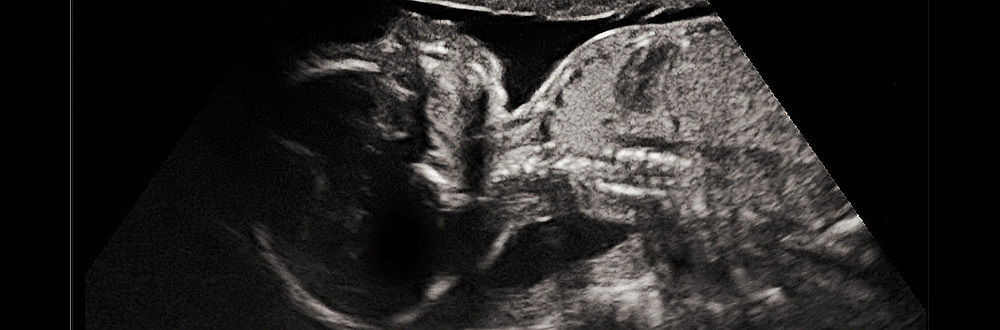

Prenatální diagnostika

Ultrazvukové vyšetření šíjového projasnění

Mezi 11. až 13. týdnem (13. týden + 6 dní) těhotenství se provádí ultrazvukové měření tzv. šíjového projasnění (nuchal translucency, NT). Šíjové projasnění způsobuje tekutina pod kůží v zátylku plodu, která je přechodně přítomna u všech plodů. U plodů s Downovým syndromem je však šířka (množství tekutiny) tohoto projasnění významně větší.